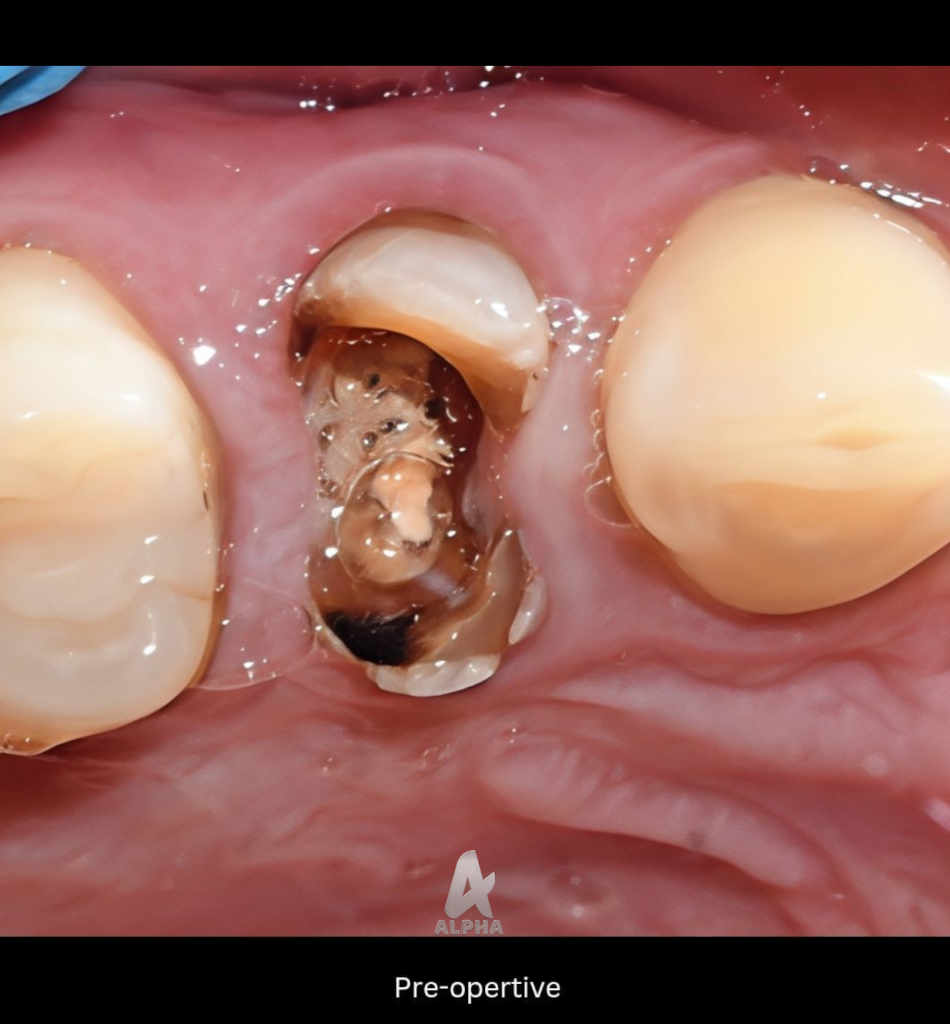

pre operative situation

1. Isolation and Pre-operative Assessment

Rubber Dam Isolation: The procedure began with strict isolation using a rubber dam to ensure an aseptic field.

Pre-operative Radiographs: Pre-operative periapical radiographs were taken to evaluate the existing treatment, identify the cause of failure (poorly condensed gutta-percha/inadequate obturation), and assess the periapical status.